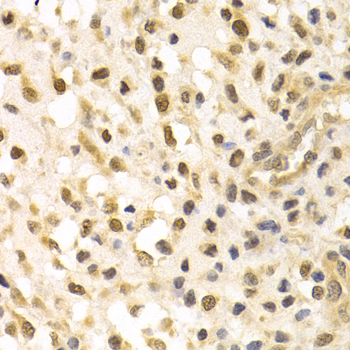

Immunohistochemistry of paraffin-embedded human metrocarcinoma using CUL4A antibody at dilution of 1:200 (400x lens).